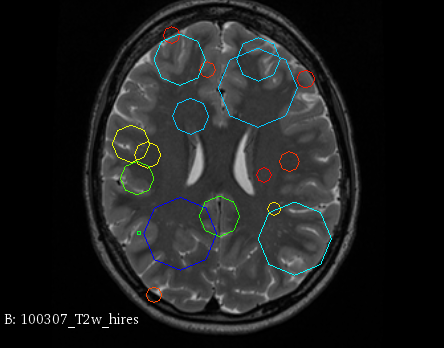

Figure 3 provides a scale-space visualization of feature matches for a single pair of MZ twins and NT siblings, where scale information is represented using the circle radius. Note that circles represent the intersection of 3D spheres with the visible slice and, thus, non-intersecting features are hidden in this 2D visualization.

It can be seen that different image modalities generally result in distinct, complementary feature correspondences throughout the brain, allowing a rich characterization of both anatomical and connectivity structure. In T1 and T2 images, features are mainly located in the frontal lobe, corpus callosum and brain stem. Smaller-scale features are also visible along various cortical regions, as well as in sub-cortical structures near the basal ganglia. Although highly correlated, T1 images show significantly more feature matches than T2 images. Moreover, images based on diffusion measures have less matches than in structural modalities. These matches are located mostly inside or near to white matter: larger-scale features in the corpus-callosum, and smaller-scale ones in the brain stem and along white matter bundles. While not shown in the figure, the set of matches found by combining two modalities (e.g., T1 + T2) generally corresponds to the union of those obtained with these individual modalities.

Comparing different sibling types, we observe a greater number of matches between MZ twins than NT siblings. This observation, which is easier to visualize in T2 and GFA images, is consistent with other analyses on twin datasets. In terms of feature location and scale, no obvious pattern can be seen when comparing these two sibling types. However, a more detailed analysis would be required to validate this assertion.